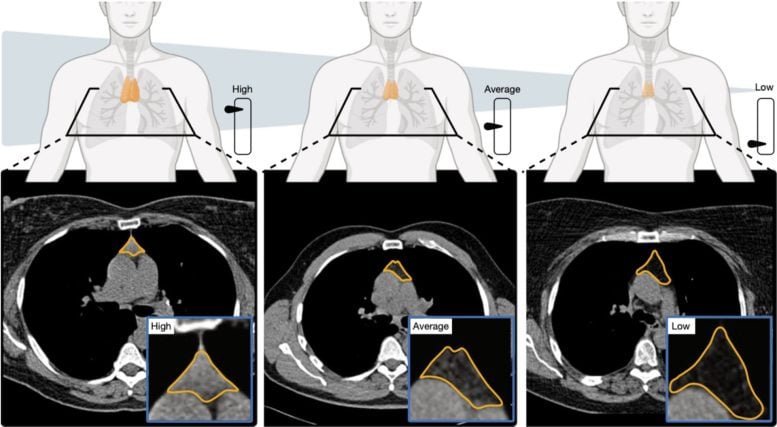

研究人员通过测量胸腺的大小、结构和成分来评估胸腺,创建“胸腺健康”评分。得分较高的个体死亡风险降低约 50%,死于以下疾病的风险降低 63%心血管疾病,与得分较低的人相比,患肺癌的风险降低 36%。即使考虑了年龄和其他健康因素,这些结果仍然成立。